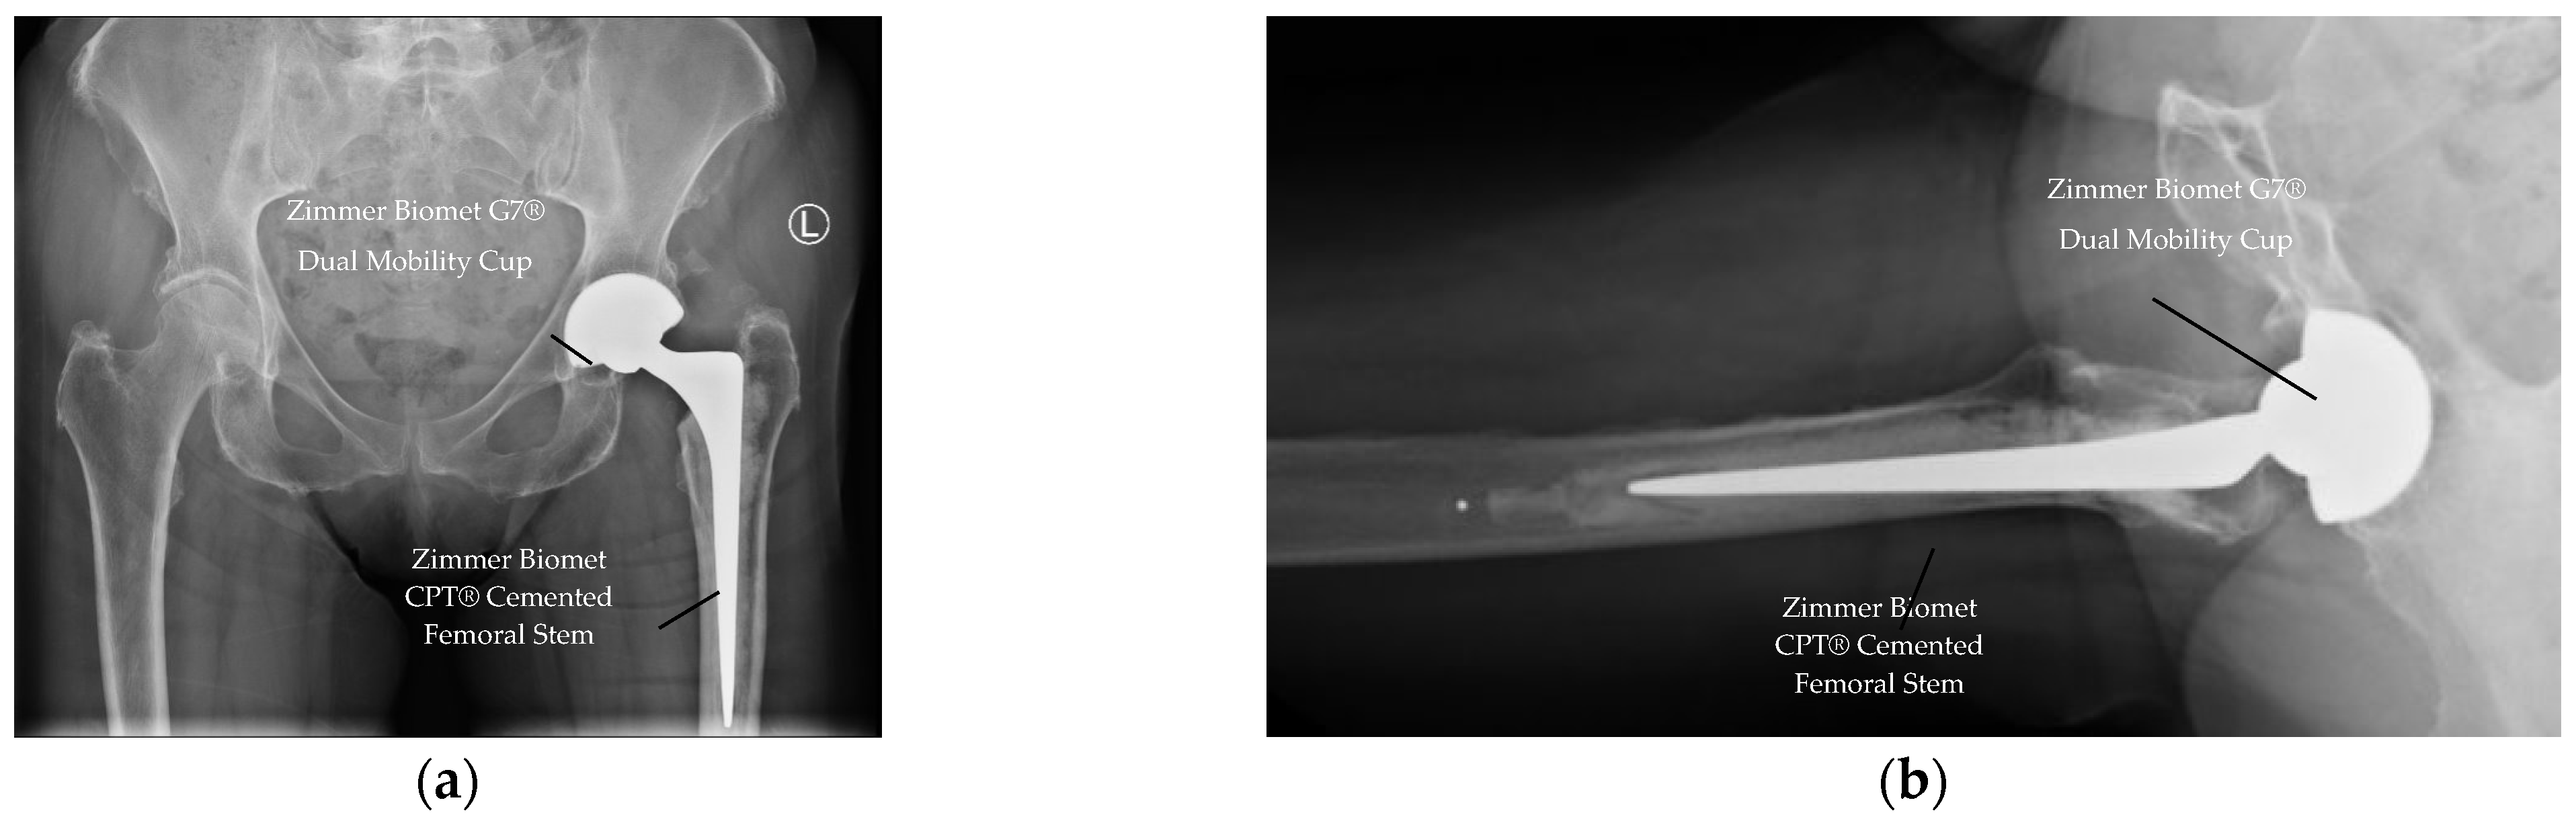

At one-year follow-up, there was no case of dislocation (0.0%) in any patient (see Table 3), demonstrating excellent stability. All radiographs demonstrated appropriate component positioning of the acetabulum cup and femoral stem, and no radiographic loosening (AP/lateral views) of the implant. See Figure 2 for example of Postoperative radiographs confirmed appropriate component positioning without loosening.

Radiographic review confirmed no cases of acetabular or femoral component loosening using the DeLee & Charnley (acetabulum) and Gruen zones (femur) classifications. One peri-prosthetic fracture (PPF) of the acetabular implant occurred in the cemented group, resulting in revision at seven months post-initial THA. Periprosthetic fractures at one year are summarised in Table 5.

Figure 2. Postoperative radiographs at one-year follow-up. (a) Anteroposterior view showing well-positioned G7® acetabular cup and cemented CPT femoral stem (left hip). (b) Lateral view confirming absence of radiolucent lines or implant migration.